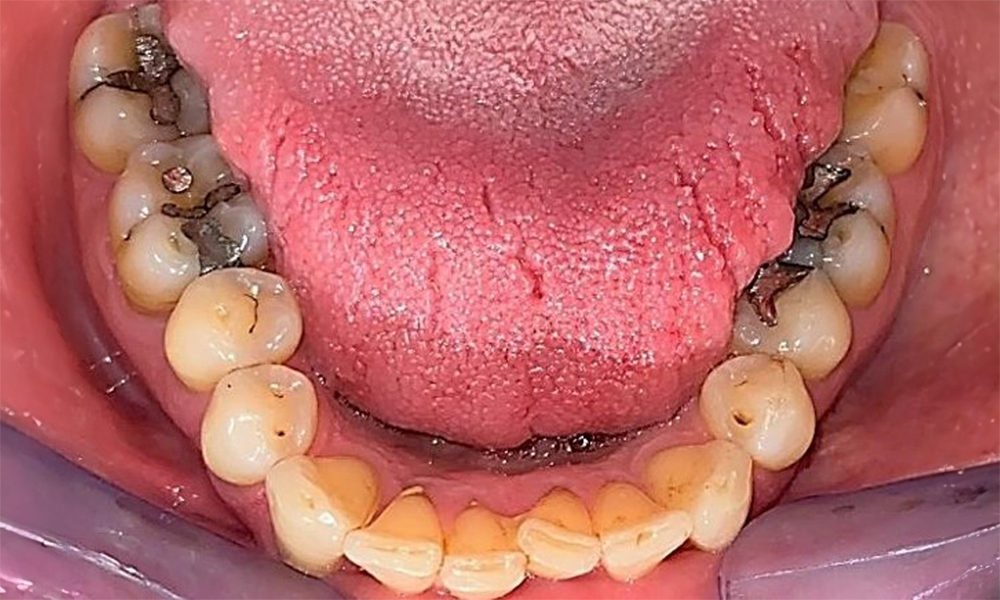

Occlusal view of the mandible showing the denture in situ.

Fig. 6 Occlusal view of the mandible showing the denture in situ. © Dr R. Krapf

The patient has a full dentition with 28 teeth, which includes amalgam and composite fillings in the molar and premolar regions. There is a visible clinical marginal gap present on tooth 14. Tooth 27 has an adequate gold inlay. There are also generalized attritions and abrasions. (Fig. 2, Fig. 3, Fig. 4, Fig. 5, Fig. 6)